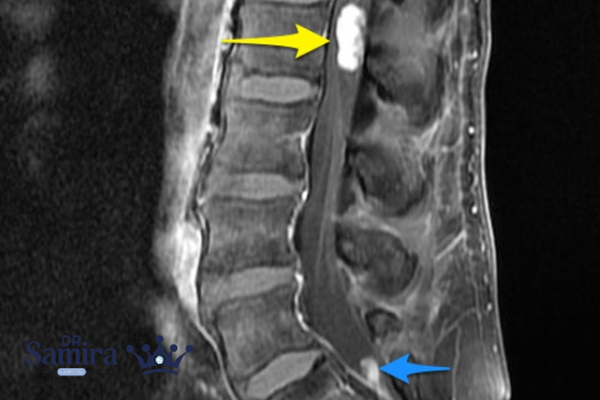

روش تشخیص میکسو پاپیلاری

مهمترین ابزار تشخیصی این بیماری MRI است. در MRI با تزریق ماده حاجب، تومور به صورت یک ضایعه مشخص در انتهای نخاع دیده میشود. MRI علاوه بر تشخیص وجود تومور، میتواند اندازه، موقعیت و ارتباط آن با رشتههای عصبی را مشخص کند.

پس از جراحی، نمونه بافتی برداشته شده زیر میکروسکوپ بررسی میشود تا تشخیص قطعی تایید گردد. در این بررسی، پزشک متخصص رادیوتراپی و انکولوژی دکتر سمیرا خالدی پاتولوژیست الگوی خاص تومور را که شامل ساختارهای پاپیلاری (شبیه انگشتک) و زمینه ژلهای یا میکسوئید است، مشاهده میکند.